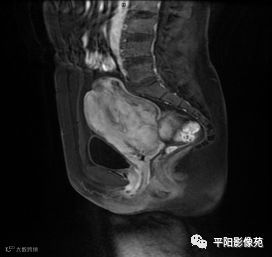

MRI表现

T2矢状位

(宫腔内见金属节育环伪影)宫颈区见不规则形等T1稍长T2信号软组织肿块,DWI序列呈明显高信号,大小约为3.87cmX2.64cm,双侧宫颈基质低信号环连续性中断,病灶向子宫右后上方生长,周围脂肪间隙模糊,增强扫描明显强化,强化程度低于子宫及宫颈实质;子宫后方、子宫直肠间隙见不规则形长T1长T2信号软组织肿块,DWI序列呈高信号,大小约10.12cmX4.82cmX10.29cm,病灶呈分叶状,向下方生长与宫颈分界不清,与直肠分界尚清,增强扫描明显不均匀强化。